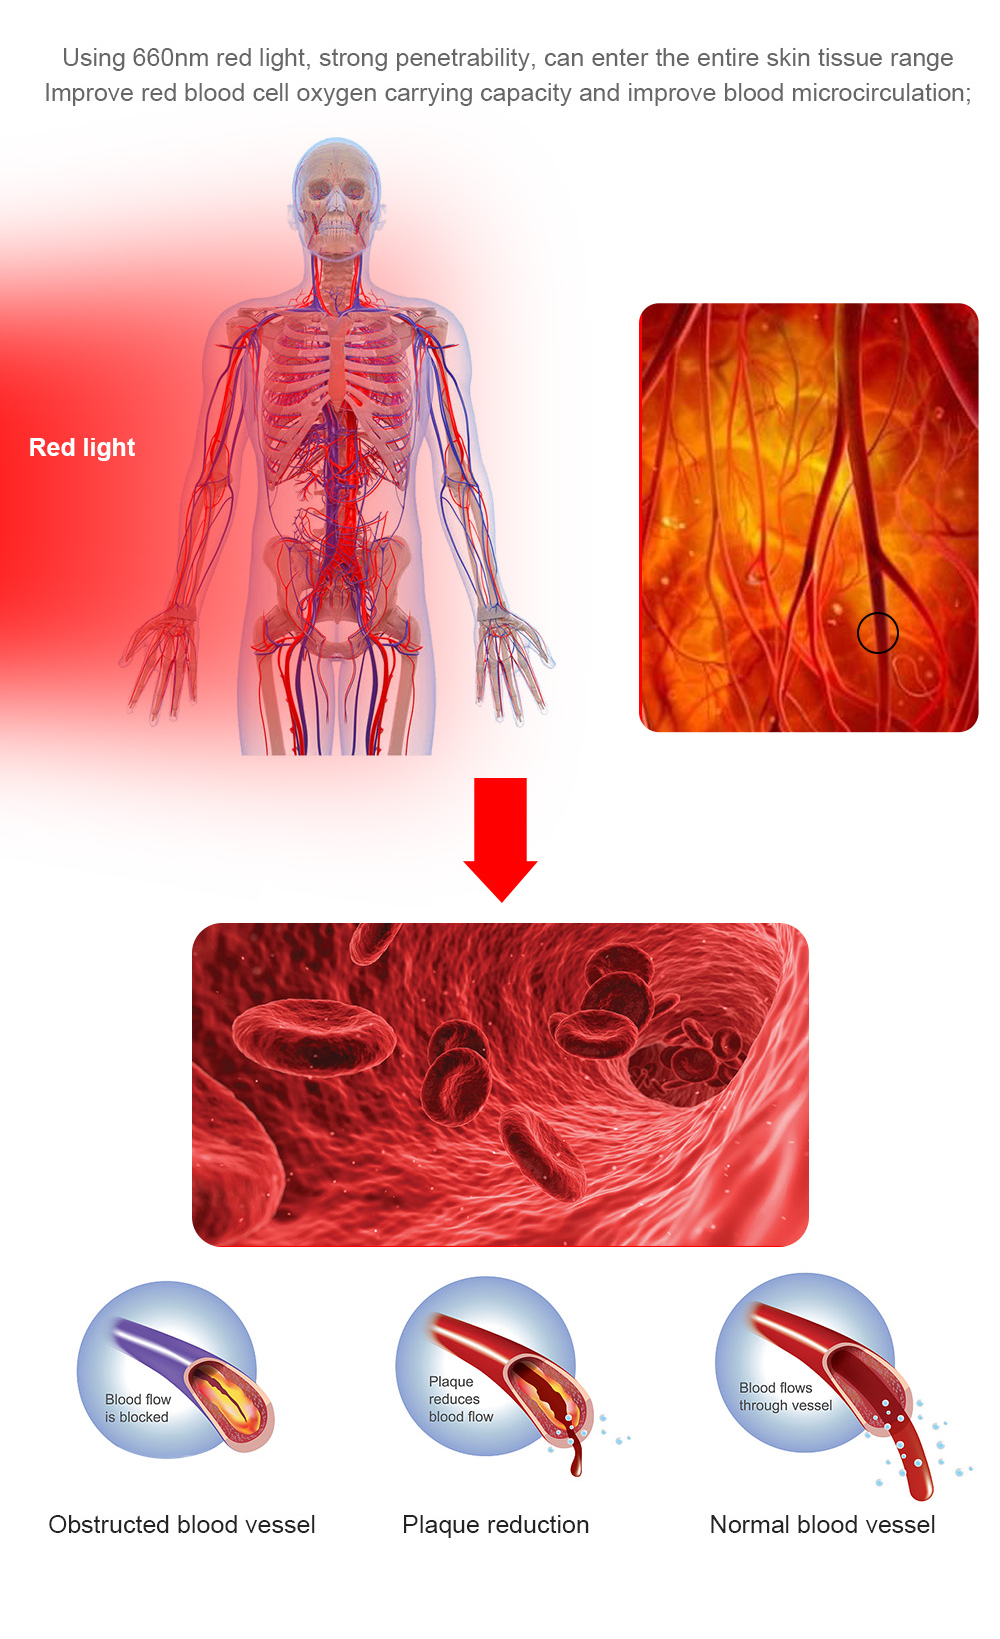

Red light therapy is also known as low-level laser therapy (LLLT). It uses low energy light emitting diodes (LEDs) or lasers as an alternative therapy for pain relief, or to promote good cell functions.

The principle of red light therapy can be thought of as like a human version of the way plants photosynthesize. It is thought that certain wavelengths of light can enhance the functioning of mitochondria, which are the organelles in a cell which take in nutrients and break them down to create energy molecules for the cell. By enhancing the cellular respiration, it will improve the functioning of the whole cell.